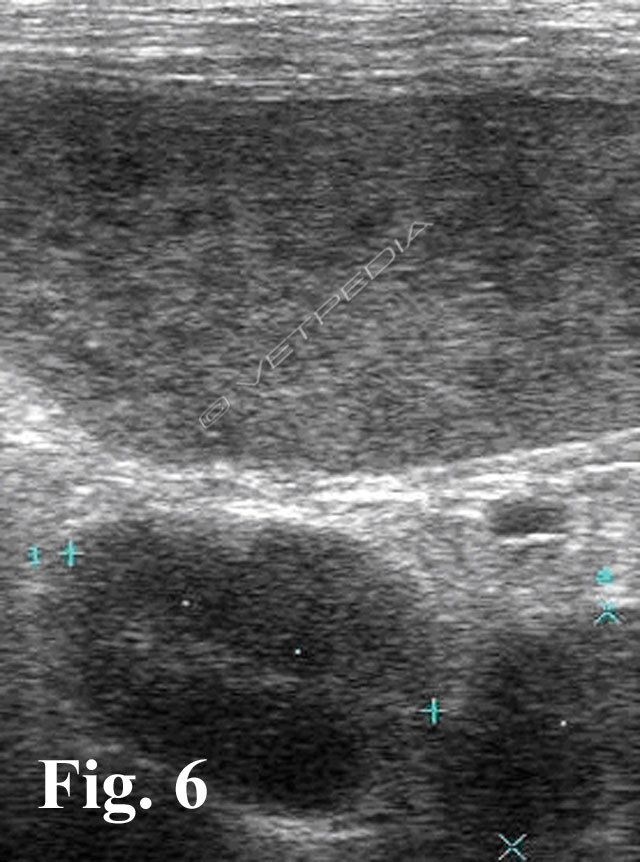

{{/_source.additionalInfo}}L’ecografia rappresenta una delle metodiche più sensibili per lo studio dei linfonodi addominali e permette di studiare la loro forma, le dimensioni, l’ecostruttura e l’ecogenicità. In tabella 1 sono riportati i linfonodi che drenano gli organi viscerali e le strutture parietali1. LINFONODI VISCERALI LINFONODI PARIETALI Lin